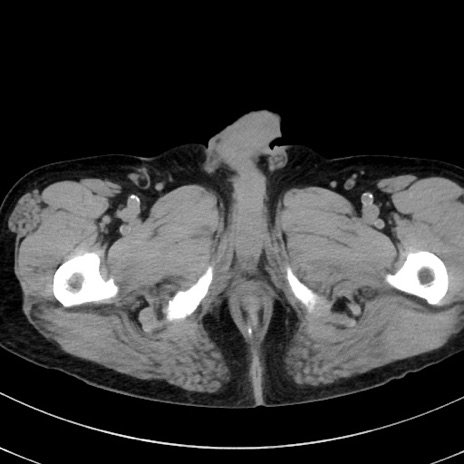

症例38(横断像)

【症例】70歳代 男性

【主訴】腹痛・嘔吐

【現病歴】昨晩より、嘔吐・腹痛あり。今朝になっても嘔吐あり。来院。

【既往歴】心臓バイパス手術、開腹胆摘、腸閉塞

【身体所見】BP 107/71mmHg、HR 116/min、腹部:平坦、軟、下腹部に軽度圧痛あり。反跳痛なし。

【データ】WBC 15100、CRP 0.32